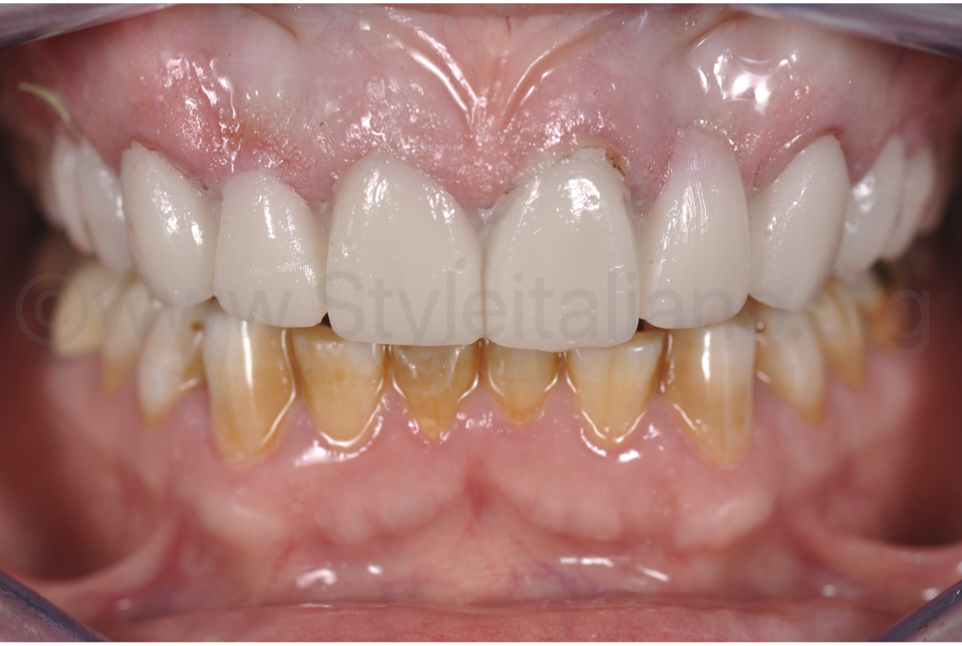

Фото 1.

55-річна пацієнтка звернулася по консультацію стосовно заміни старого металокерамічного мостоподібного протеза.

Фото 2.

На рентгенограмі хронічних інфекцій в області девітальних зубів не виявлено. Перший запропонований план лікування передбачав повне відновлення всіх зубів, оскільки вони суттєво зносилися, але пацієнтка не погодилася через матеріальні обставини. Другий план передбачав відновлення верхнього зубного ряду, щоб можна було збільшити вертикальний вимір оклюзії та отримати змогу покращити естетичний результат.

Заплановано встановити мостоподібний протез із шести елементів – від зуба 13 по 23, коронки – на зубах 24, 25, 14, 15, та оклюзійні вініри – 16, 17, 26, 27. Стосовно ясенної естетики, необхідно провести невелику гінгівектомію, щоб покращити вигляд плоскої пришийкової зони зуба 21. Приясенний профіль зубів 22 та 12 слід формувати дуже ретельно, щоб він мав ідеальний вигляд.